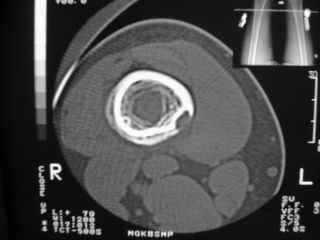

Здравствуйте, уважаемые коллеги!Представляю вашему вниманию интересный случай и пока что непонятный для меня в диагностическом плане. На днях в наше отделение (детской ортопедии и травматологии) поступил 13-летний мальчик по направлению из поликлиники с диагнозом: остеома нижней трети правого бедра.

Анамнез практически никакой: в следствие травмы (растяжение связок коленного сустава) от 07.11.2004 выполнены Rg-граммы в травмпункте и обнаружено опухолевидное образование. Первичные Rg-граммы я не публикую, так как они заметно худшего качества, да и динамики за прошедшие три недели не отражают. Болевой синдром купирован в течение трёх дней. В настоящий момент мальчика ничего не беспокоит. Ходьба не нарушена, опухоль пальпируется с трудом по задней поверхности в н\3 правого бедра, пальпация безболезненна, объем движений в суставах правой нижней конечности полный и симметричный. Кожа над опухолью не изменена.В нашей клинике проведено дополнительное обследование: общие анализы крови и мочи, биохимия крови без особенностей. Выполнены Rg-граммы на цифровом Siemens обычные и продольные томограммы срезами 3-5 мм, а также компьютерная томография поперечными срезами по 5 мм. Прошу обратить внимание, что на приведённых томограммах видны две полости 10х15 мм и 15х60 мм. Также имеются два опухолевидных образований наслаивающихся друг на друга: уплощённое и вытянутое 10х100 мм и элипсовидной формы 15х30 мм. Это хорошо заметно на фото a_1.jpg c_1.jpg и d_1.jpg. Плотность внутри полостей 125% от плотности костномозгового канала, плотность наружного опухолевидного образования 55% от плотности кортикального слоя. Также отмечается линия перелома по центру наружного опухолевидного образования.Исходя из полученных данных мнения в плане диагноза несколько разделились от 1)сочетания кортикальной фиброзной дисплазии и латентно протекавшего маршевого перелома н\3 правого бедра до 2)остеосаркомы. В отношении первого варианта не сходится отсутствие клиники при переломе такой крупной кости как бедро, второй вариант вообще оставлю без комментария, ибо некомпетентен. Хотелось бы услышать мнения коллег, с удовольствием ознакомлюсь с любыми предположениями и замечаниями.С уважением, Александр Е. КлоковОтделение детской ортопедии и травматологииБСМП г. Мурманска.